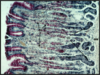

Alimentation means giving nourishment; hence the older alternative name of alimentary canal for gastrointestinal tract. This light micrograph depicts a cross section of the ileum. The four layers, namely, mucosa (M), submucosa (SM), muscularis externa (ME), and serosa (S) are visible. Muscularis externa subdivides into two layers, inner circular (IC) and and an outer longitudinal (OL). L, lumen.